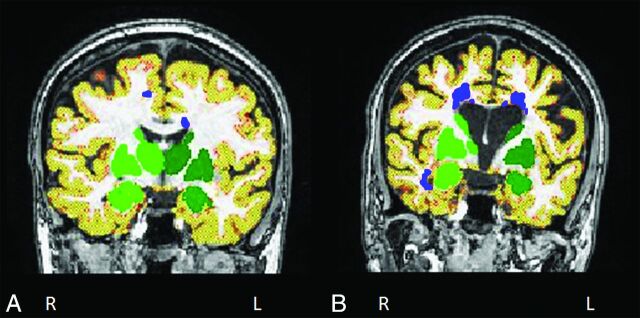

Normalized brain volume, normalized GM volume, normalized cortical GM volume, and normalized WM volume were measured on 3D T1-weighted scans by using FSL SIENAX (http://fsl.fmrib.ox.ac.uk/fsl/fslwiki/SIENA) after refilling of T1-hypointense lesions.23 Automatic segmentation of the thalamus, caudate, putamen, pallidum, hippocampus, amygdala, and accumbens was performed on 3D T1-weighted scans by using the FMRIB Integrated Registration and Segmentation Tool (FIRST; http://fsl.fmrib.ox.ac.uk/fsl/fslwiki/FIRST) software (Fig 1).24 The volume of these structures was multiplied by the head-normalization factor derived from SIENAX.

Fig 1.

Illustrative examples of segmentation of cortical gray matter volume (in red-yellow), deep gray matter volume (in green), and lesions (in blue) in patients with multiple sclerosis without (A) and with (B) cognitive impairment. Images are in radiologic convention.